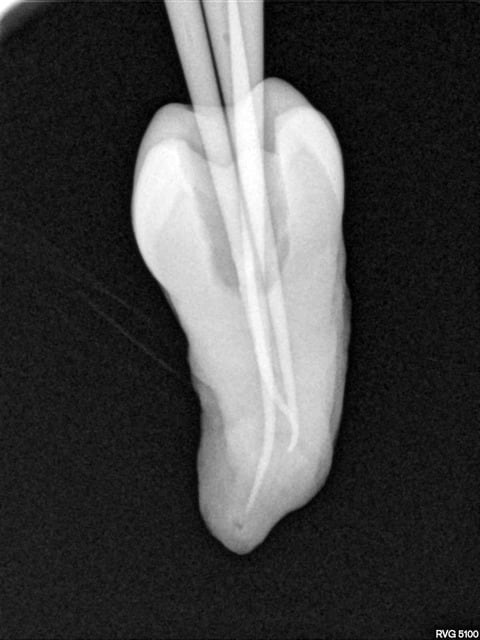

Une belle instrumentation en mésial, quelle tristesse.

Tout allait bien en progressant à patte de velours jusqu'à l'alésoir 30-4 trop fatigué apparemment (FKG Race), et j'ai donné un peu trop de force dans la progression verticale.

J'ai essayé de déloger la lime, j'ai cassé la deuxième puis la troisième.

Bon le canal est propre à défaut d'être étanche.